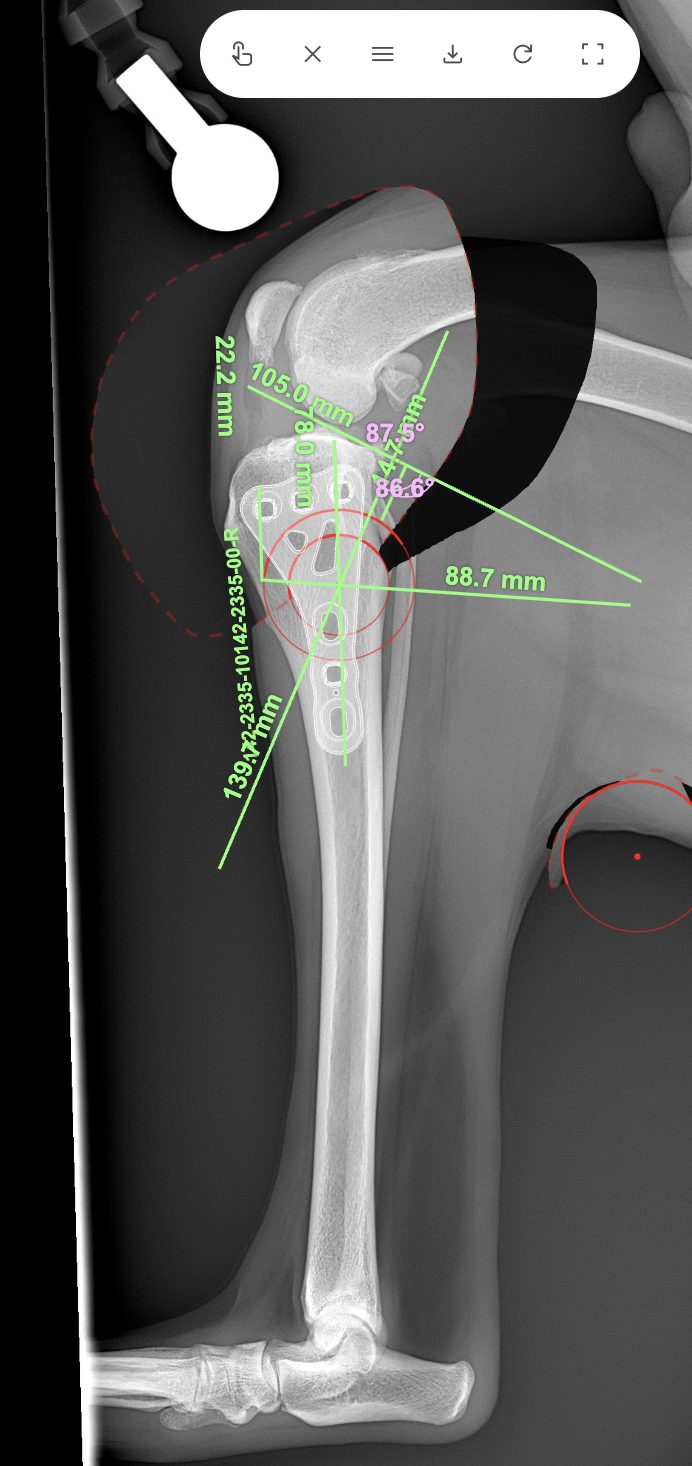

大型犬の前十字靭帯疾患(慢性経過)に対するCBLO #254 大型犬のCrCLDの患者さんに3.5 Rita Locking CBLOで対応しました。今後はリハビリテーションが非常に重要になります。生涯にわたって膝関節のケアを行なっていく必要があります。 症例カテゴリー 放射線治療整形外科軟部組織外科脳神経外科内科腫瘍外科救急・集中治療リハビリテーション科腫瘍内科内視鏡科脳神経科呼吸器外科中医・漢方猫の腎移植循環器科